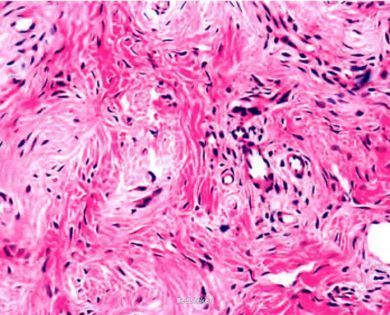

皮肤科检查:左侧鼻翼见一暗红色圆顶丘疹,直径约3 mm.表面光滑.中央轻度毛细血管扩张,质地中等,边界清楚,基底部皮肤正常。手术切除丘疹后行组织病理检查:病变呈外生性,角化过度,棘层增厚,真皮内胶原纤维增生.排列成巢状,其间可见增生、扩张的薄壁血管,并见散在的星状细胞。

诊断:鼻部纤维性丘疹。行手术治疗。